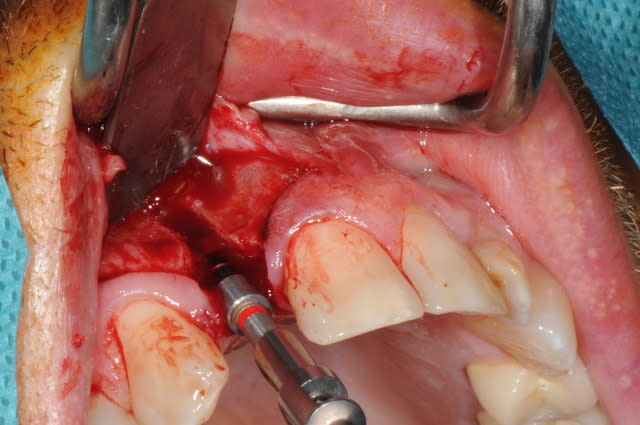

Salut, voila les photos de la chirurgie. rien d'extraordinaire , mais si certains ont des conseils, je suis preneur, j'ai la même chose à faire samedi matin

Pourriez vous me dire ce que vous utilisez pour éroder le mur palatin et éviter un axe trop vestibulaire?